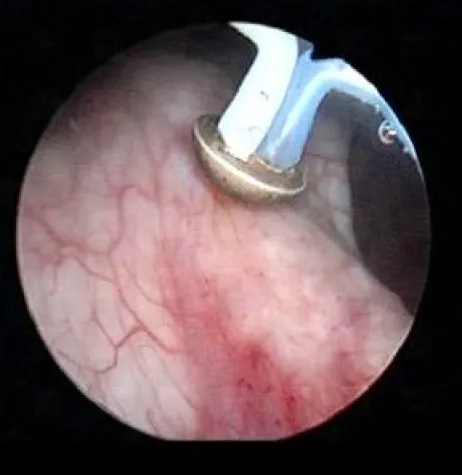

Der Operateur kann mit dem innovativen System zwei verschiedene Techniken kombinieren: die Abhobelung (Resektion) mit Hilfe von elektrischem Strom und die Verdampfung (Vaporisation) durch den Einsatz einer Vaporisationselektrode. Die Plasma-Vaporisationselektrode verdampft ähnlich wie ein Laser das Gewebe, allerdings ohne starke Hitzeentwicklung. Gleichzeitig wird das Gewebe verschorft und dadurch Blutungen von vorne herein vermieden Die Vaporisationselektrode wird hauptsächlich im Bereich der stark durchbluteten Schleimhäute eingesetzt. „Das dahinter liegende Prostatagewebe ist von weniger Blutkapillaren durchzogen und kann nun mit der elektrischen Schlinge abgehobelt werden“, erläutert der Kölner Urologe. Die Gewebespäne, die bei der Resektion anfallen, können vom Pathologen auf Tumorzellen untersucht werden.

Durch die einmalige Kombination von Verdampfung und elektrischer Schlinge kann je nach Bedarf, das heißt, ob die Blutstillung oder die Gewebeentnahme im Vordergrund steht – die jeweilige Elektrode ausgewählt und über den Arbeitskanal in die Prostata eingebracht werden. Ein weiterer Pluspunkt ist die verkürzte Operationszeit. „Das macht das Verfahren vor allem für Patienten attraktiv, die zu einem hohen Blutungsrisiko neigen und an Begleiterkrankungen wie Herz-Kreislauferkrankungen leiden.